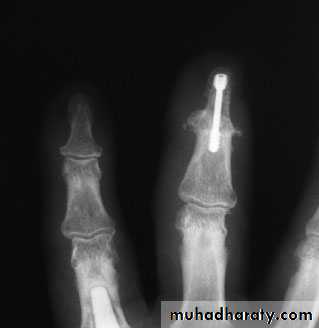

If a phalanx or entire digitis duplicated, removal and soft-tissue reconstruction

Duplications of the thumb or central digits:

extremely rare

require complex reconstructive surgery of the digit, its tendons and the overlying skin.